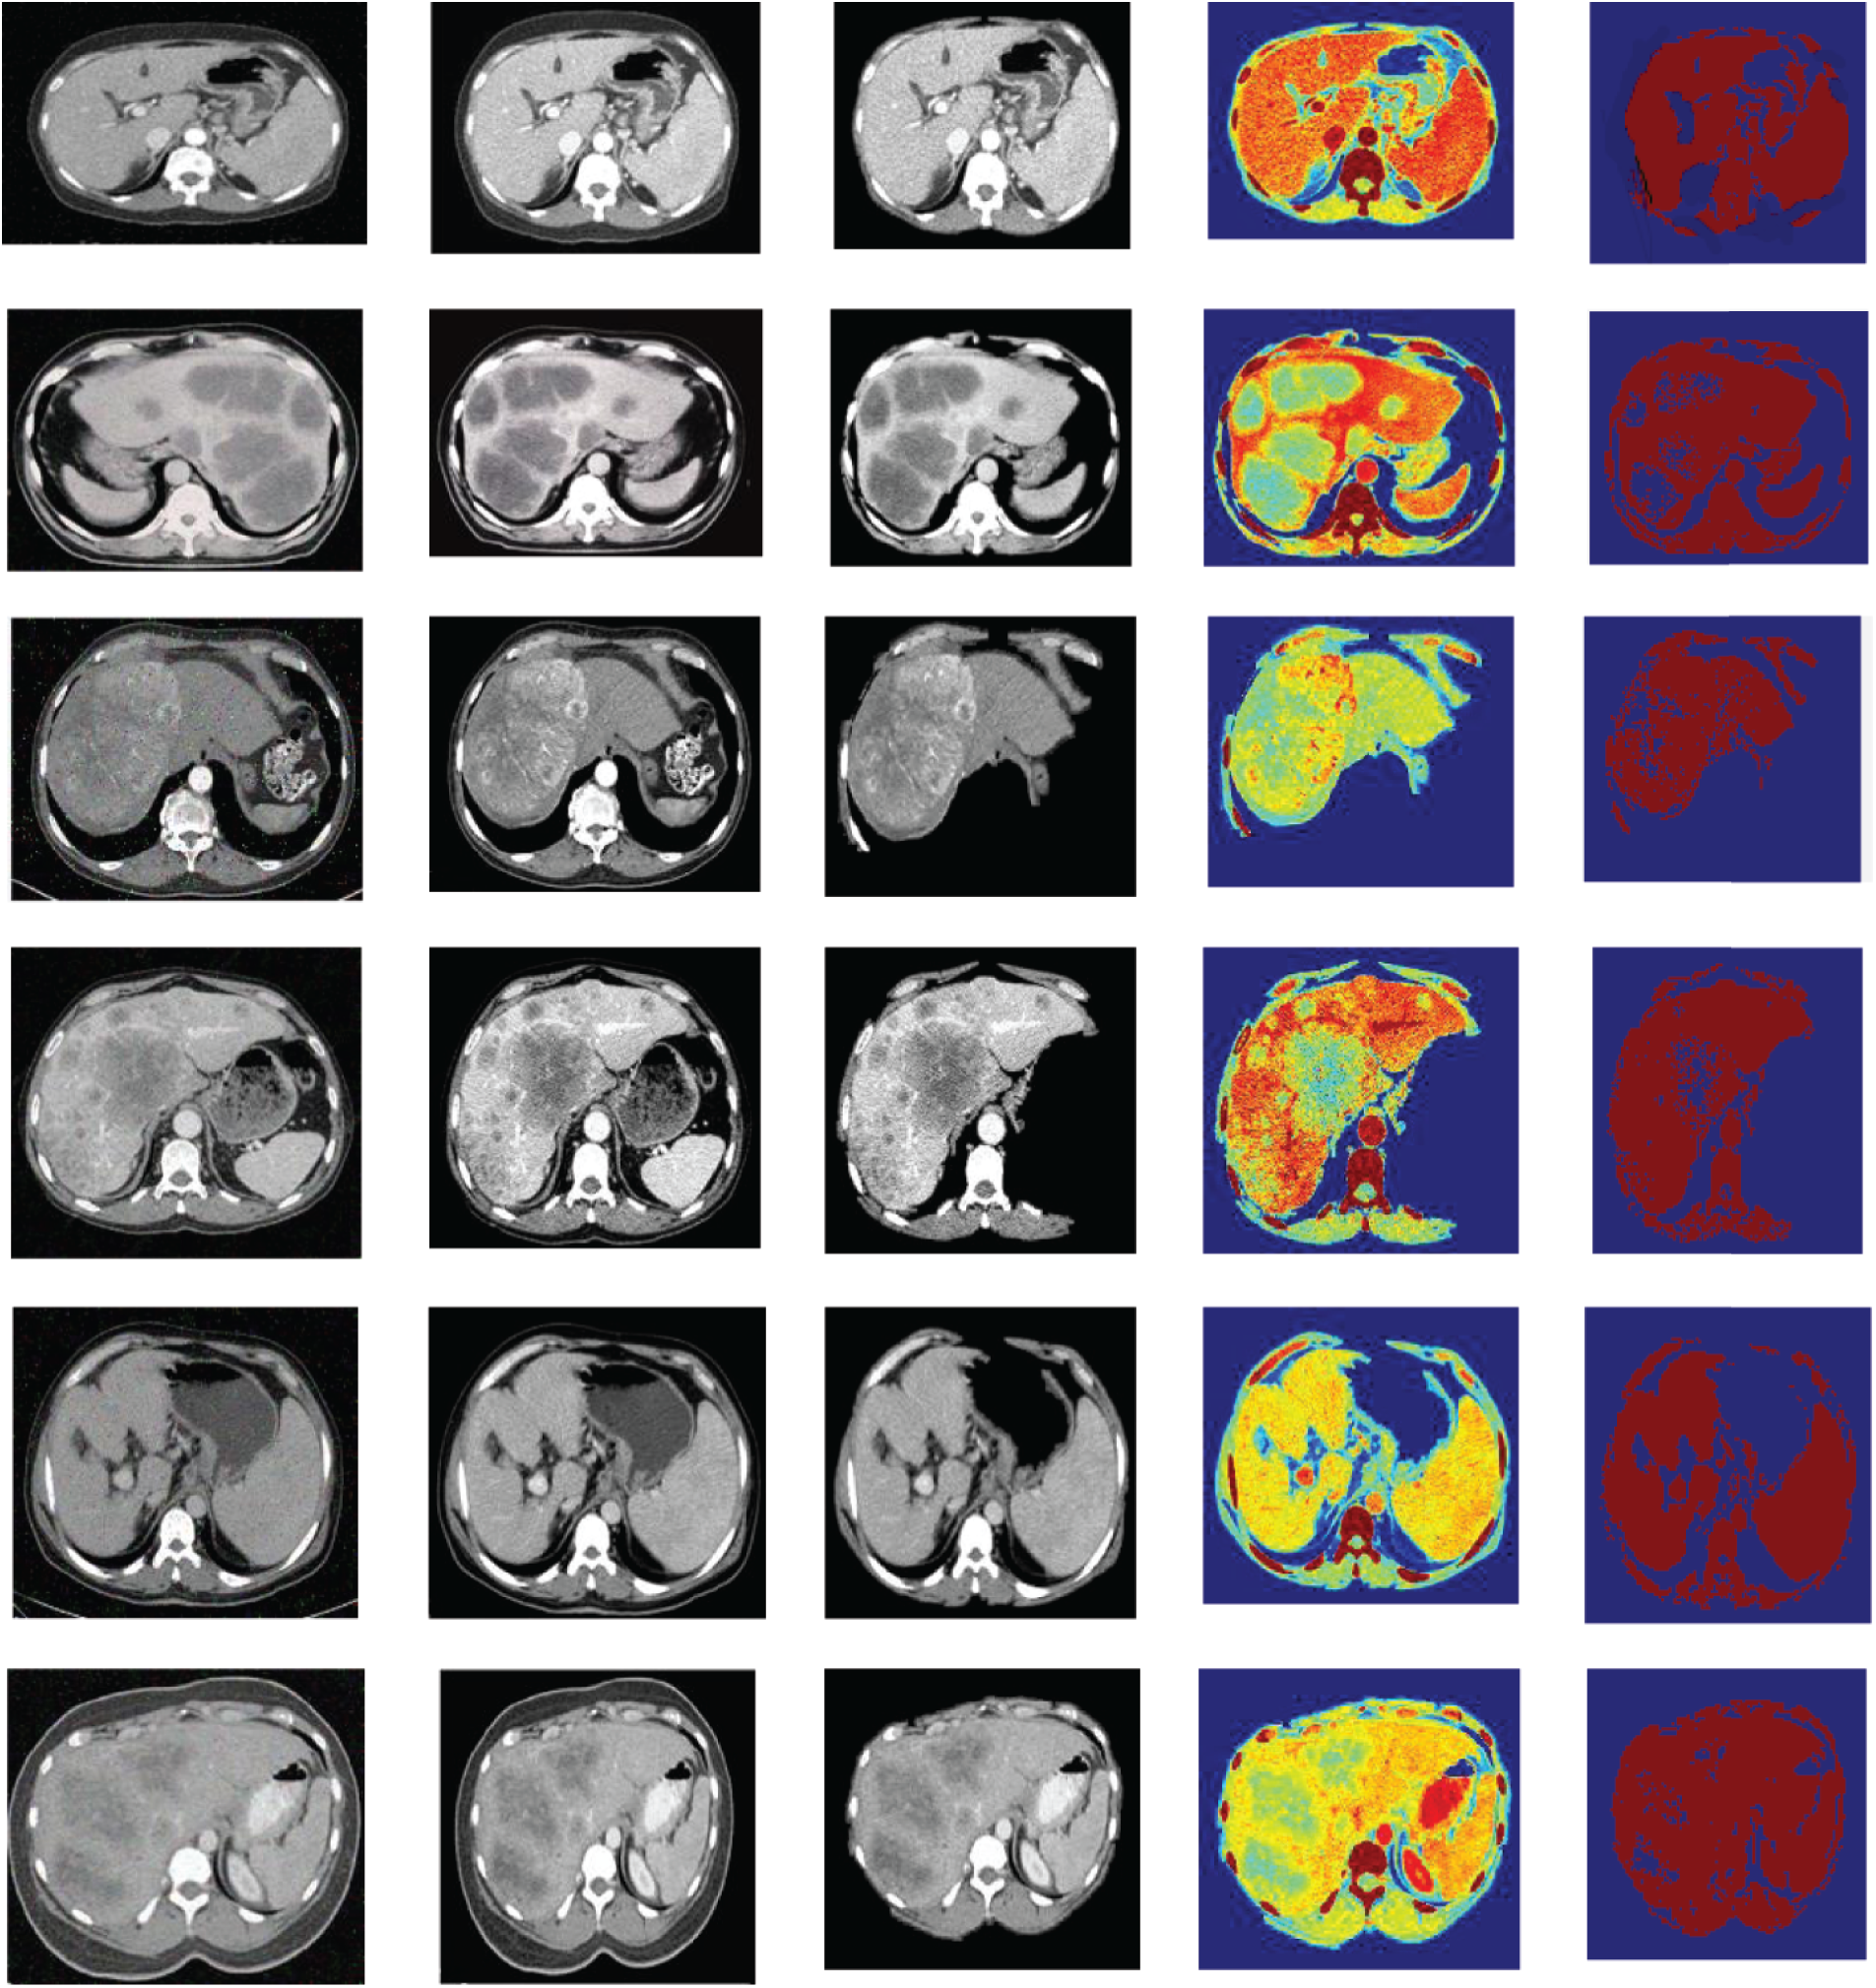

Figure 3: The resultant outcomes of the proposed AW-HARIS approach

In Fig. 3, the leftmost image is the original CT image acquired from the equipment, and the second image from the left represents the de-noise and contrast-enhanced image. The third image is the stripped image for removing the unwanted abdominal tissues. The image next to it represents the segmented image on applying the color-map to the resultant image. The final image is the segmented image with a threshold value of 75. The resulting segmented image is more pleasing when the threshold is appropriately chosen. The color-map is being generated based on the intensities of the underlying tissue are at various grey-level values. The colors-mapping with different grey-level intensities for the segmented image for ease of identification of the abnormal region, the region this is affected is highlighted in the pale green color. As the colormap is applied over the pixel intensity ranges, the neighboring pixels share almost the same color. The actual region of interest can be recognized easily by using the thresholding over the resultant image.